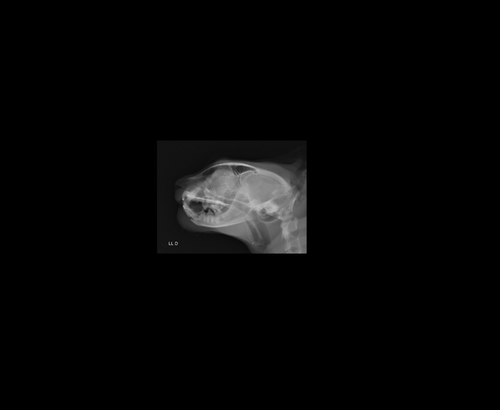

Oi eu sou a Liu, criei essa vakinha pra poder operar o meu filho peludo de nome Nego, ele é um gatinho lindo e muito dócil, adora dormir na janela e isso infelizmente causou um acidente horrível, nós temos tela de proteção em todas as janelas porém no domingo as 20:30 enquanto ele dormia na janela uma corda da tela arrebentou e ele caiu da janela do 5° andar, foram muitos metros de queda e ele acabou fraturando a mandíbula, já gastei tudo com a internação e exames mas os veterinários dizem que ele tem que se operar com urgência pra poder se alimentar e parar de sentir dor, qualquer ajuda é bem vinda e serei extremamente grata a todos, segue em anexo o que preciso para realizar a cirurgia e as radiografias do crânio dele.